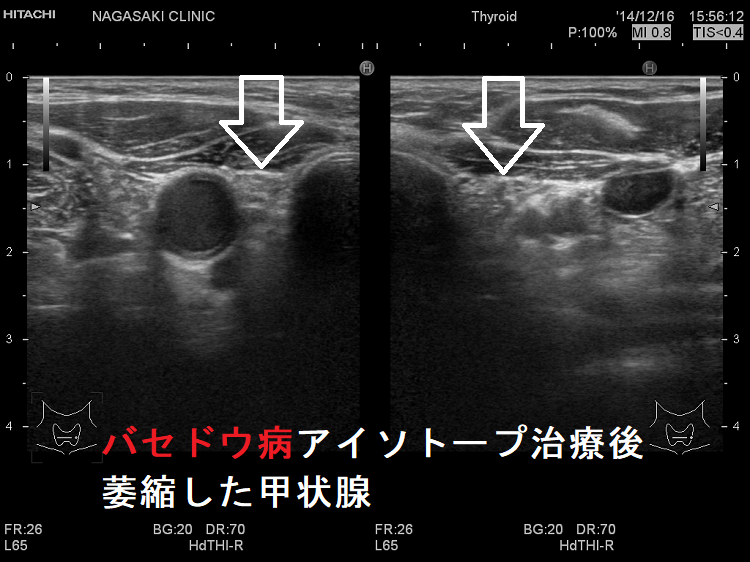

RAI 治療は甲状腺の大部分またはすべてを破壊します。これは、RAI治療後は甲状腺ホルモン補充薬を生涯にわたって服用する必要があることを意味します。